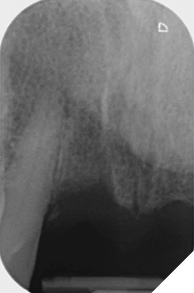

Radiographic examination shows the upper left lateral incisor tooth has decayed through and through and the upper right central incisor tooth is heavily root treated and filled (Figs. 1-2).

The existing metal ceramic bridgework was thick and bulky, but the patient was used to it. The patient also didn’t have any pain or discomfort yet from the slightly loose bridge or dental caries. The patient was most concerned the bridge would suddenly come out and would have a space (Figs. 3-4).